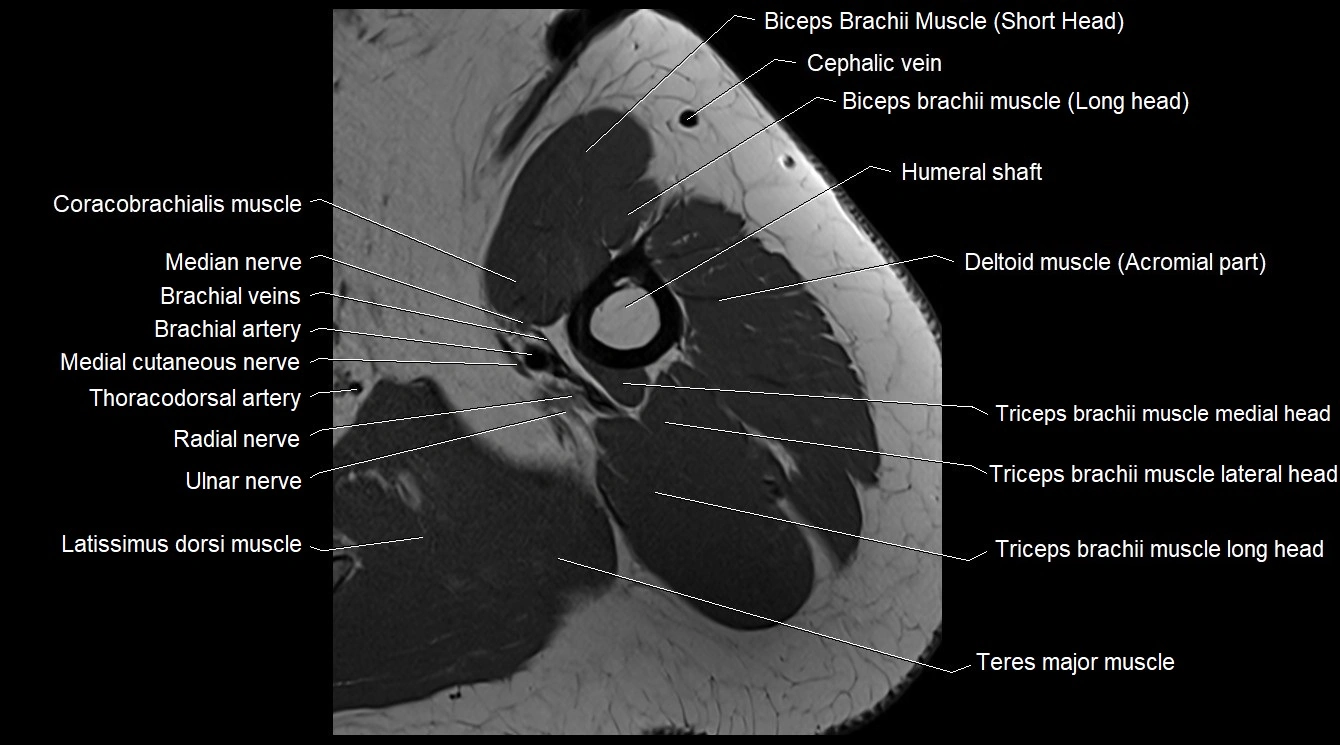

- Biceps brachii muscle

- Brachialis muscle

- Cephalic vein

- Coracobrachialis muscle

- Median nerve

- Radial nerve

- Ulnar nerve

- Teres major muscle

- Triceps brachii muscle

- Long head of triceps brachii muscle

- Lateral head of triceps brachii muscle

- Medial head of triceps brachii muscle